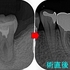

治療2回目 2個あったフィステルも無くなっていたので根管充填+レジンコアまで

2025 EEdental KOE (2).jpg

根管充填材はガッタパーチャー使用

*基本的に私は根管充填材はMTAが良いとは思っていませんので、ケースを選んでしか使っていません。